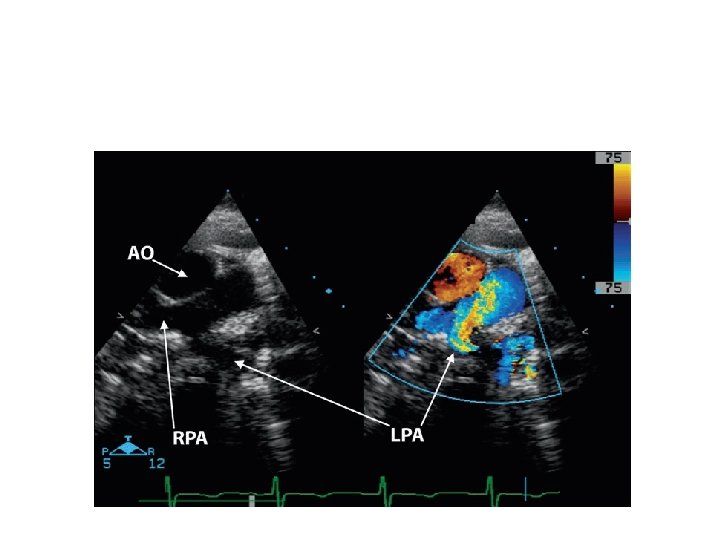

PA from Asc. Aorta • MPA arises from heart • RPA or LPA arises from ascending aorta • RPA-more common -82%

• Anomalous RPA -abnormal migration -aortopulmonary septation anomalies, IAA • Anomalous LPA - Failure to join TA sac -RAA and TOF • Differential pulmonary blood flow • CCF in infancy f/b development of PVR